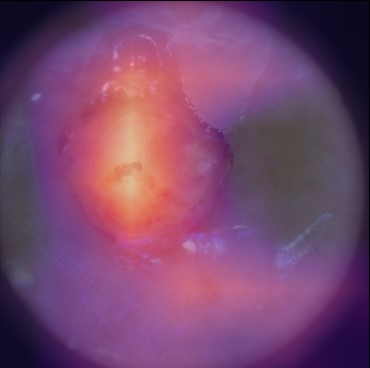

State-of-the-art deep learning approaches for skin lesion recognition often require pretraining on larger and more varied datasets, to overcome the generalization limitations derived from the reduced size of the skin lesion imaging datasets. ImageNet is often used as the pretraining dataset, but its transferring potential is hindered by the domain gap between the source dataset and the target dermatoscopic scenario. In this work, we introduce a novel pretraining approach that sequentially trains a series of Self-Supervised Learning pretext tasks and only requires the unlabeled skin lesion imaging data. We present a simple methodology to establish an ordering that defines a pretext task curriculum. For the multi-class skin lesion classification problem, and ISIC-2019 dataset, we provide experimental evidence showing that: i) a model pretrained by a curriculum of pretext tasks outperforms models pretrained by individual pretext tasks, and ii) a model pretrained by the optimal pretext task curriculum outperforms a model pretrained on ImageNet. We demonstrate that this performance gain is related to the fact that the curriculum of pretext tasks better focuses the attention of the final model on the skin lesion. Beyond performance improvement, this strategy allows for a large reduction in the training time with respect to ImageNet pretraining, which is especially advantageous for network architectures tailored for a specific problem.

翻译:在皮肤损伤识别方面,最先进的深层学习方法往往要求就更大规模、更多样化的数据集进行预先培训,以克服因皮肤损伤成像数据集规模缩小而产生的一般限制。图像网通常用作预培训数据集,但其转移潜力受到源数据集和目标皮肤科情景之间领域差距的阻碍。在这项工作中,我们采用新的预培训方法,按顺序培训一系列自我监视学习的借口任务,只要求不贴标签的皮肤损伤成像数据。我们提出了一个简单的方法,以建立一个命令来界定一个托辞任务课程。对于多级皮肤损伤分类问题和ISIC-2019数据集,我们提供了实验性证据,表明:一) 由一个托辞任务课程比个人托辞任务预先训练的模式更优于模型,这在图像网上培训模型比模型先培训更优于模型。我们证明,这一业绩收益与以下事实有关:一个更突出托辞任务的重点,即界定一个托辞任务课程,确定一个托辞任务大纲。对于多级皮肤损伤分类问题,以及ISIC-2019数据集,我们提供了实验性地证明:一模型预设的模型的模型预设型模型预训练模型,使得最终的升级模型能够改进。